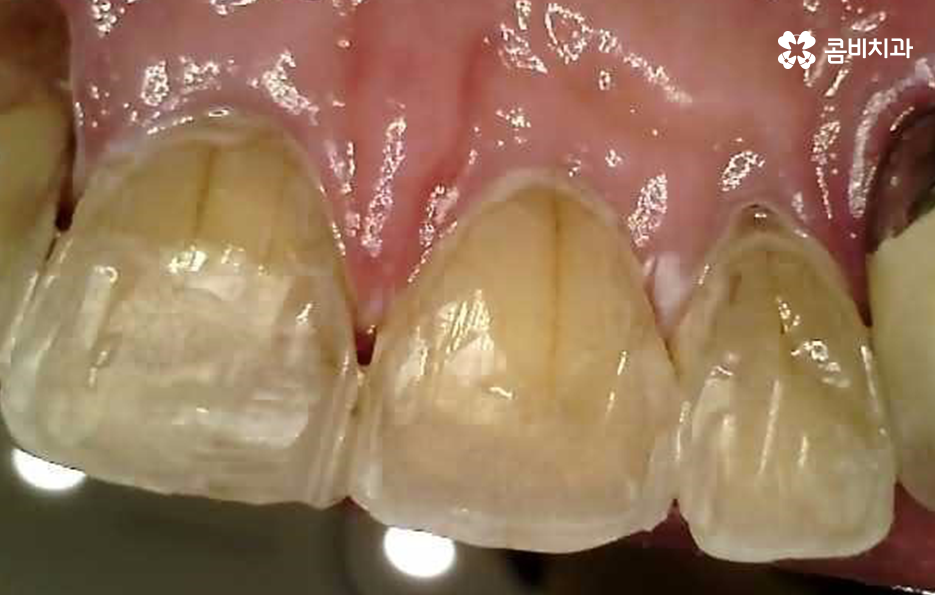

또한 60대 이후 노인 분들의 경우 치아 자체도 수명이 줄어든 상태지만 잇몸이 이미 많이 내려 앉아서 치아의 뿌리 쪽이 외부에 드러나면서 이가 시리고 흔들려서 고생하는 경우가 많을 거예요